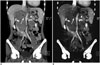

Using contrast-enhanced dual energy CT data in all body regions, iodine map specifically shows iodine distribution in tissues with improved iodine contrast-to-noise ratio, but the bone and calcium are also included in the map (Figs. 8, 9). In the thoracic region, dual-energy lung parenchymal iodine or pulmonary blood volume (PBV) map, as a surrogate of lung perfusion, is mainly used to improve the diagnosis of pulmonary thromboembolism. By this method, characteristically wedge-shaped iodine-deficient lung lesions are detected, which are not apparent on conventional pulmonary CT angiography (Fig. 7) (26, 27, 28). In pulmonary thromboembolism, dual-phase dual-energy PBV map can be used to differentiate between acute and chronic phases by identifying delayed systemic collateral flow at the expense of higher radiation dose (29). Dual-energy PBV map can demonstrate that endothelial dysfunction represented with hypoxic peripheral arteriolar vasoconstriction is reversible after administration of oral sildenafil, supported by reduced PBV coefficients of variation due to lung perfusion heterogeneity, in smoking-associated emphysema (30).

|

In all body regions, due to improved lesion-to-background contrast, enhancing lesions or vessels are more conspicuous on the iodine map (Fig. 8). Iodine map is helpful not only to distinguish a particularly hyperdense, cystic lesion or hematoma from enhancing lesion, but also to clearly delineate the extent of bowel ischemia (14, 18, 25); in addition, malignant tumors may be more accurately differentiated from benign tumors based on the degree of iodine enhancement (19). Treatment response may be assessed quantitatively by measuring the iodine concentration in enhancing tumors in oncologic patients (14, 18, 28, 31).